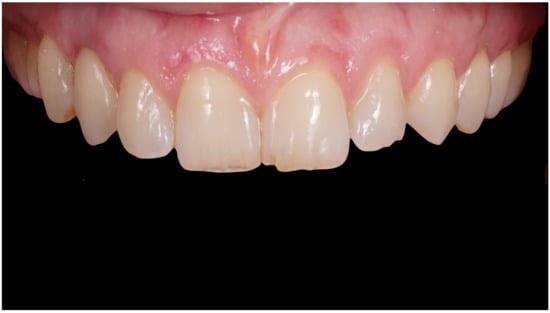

Definitive crown after 1 year of follow-up, frontal view.

Figure 10.